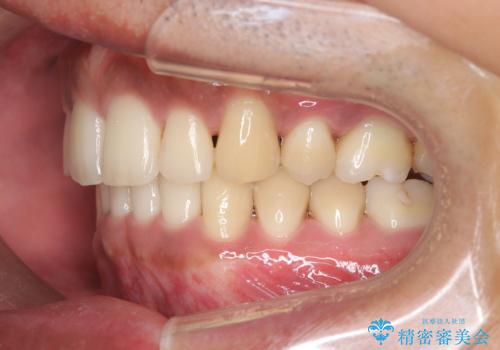

- 前歯のデコボコ(叢生)と、上下の歯の重なりが深い「ディープバイト(過蓋咬合)」を主訴にご来院されました。精密検査の結果、歯が並ぶスペースが不足しているため、上顎左右の小臼歯を抜歯することでスペースを確保し、全体の咬み合わせを改善する治療計画を立案しました。これにより、見た目の改善だけでなく、過度な咬み合わせによって生じる歯や顎への負担も軽減することを目指します。

今回の矯正治療では、まず歯が並ぶスペースを確保するため、上顎の小臼歯を抜歯しました。抜歯によってできたスペースを利用して前歯を奥へ移動させ、デコボコを解消。同時に、奥歯の咬み合わせを調整することで、深すぎた咬み合わせであるディープバイトも改善しました。治療の結果、長年気にされていた前歯のデコボコが解消され、理想的な歯並びに。さらに、正しい咬み合わせを獲得したことで、機能的にも安定した美しい口元になりました。